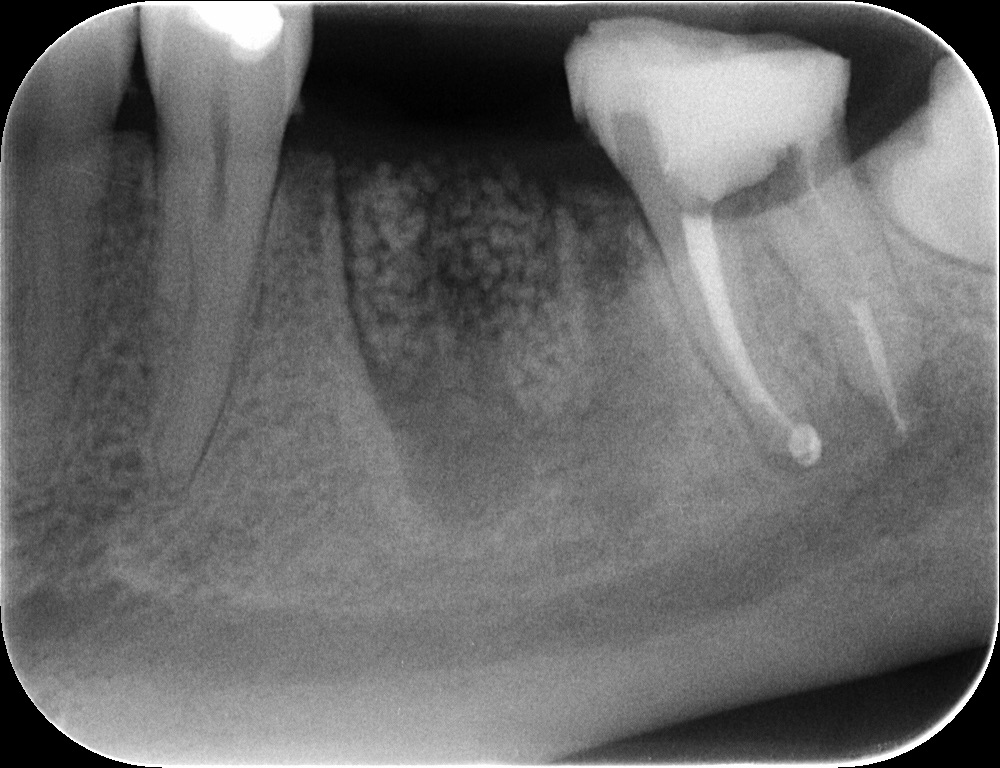

Pani Malwina z Chorzowa zgłosiła się z powodu stanu zapalnego w dolnym zębie trzonowym, ze względu na zaawansowanie procesu niemożliwie było uratowanie zęba i podjęto decyzję o jego usunięciu. Żeby zabezpieczyć kość pod planowany w przyszłości implant bezpośrednio po usunięciu zęba zregenerowano kość biomateriałem, aby potem wykonać zabieg implantacji i bezpiecznie posadowić koronę na implancie. Dzięki wykonanej regeneracji kości w dentestica Katowice podłoże kostne pod implant jest stabilne i zapewnia prawidłowe, długofalowe funkcjonowanie odbudowy na implancie. Bardzo ważne jest aby usuwać z organizmu stany zapalne i jednocześnie planować odbudowę podparcia kostnego pod przyszłe zęby, ponieważ brak nawet pojedynczego zęba zaburza funkcję całej jamy ustnej.